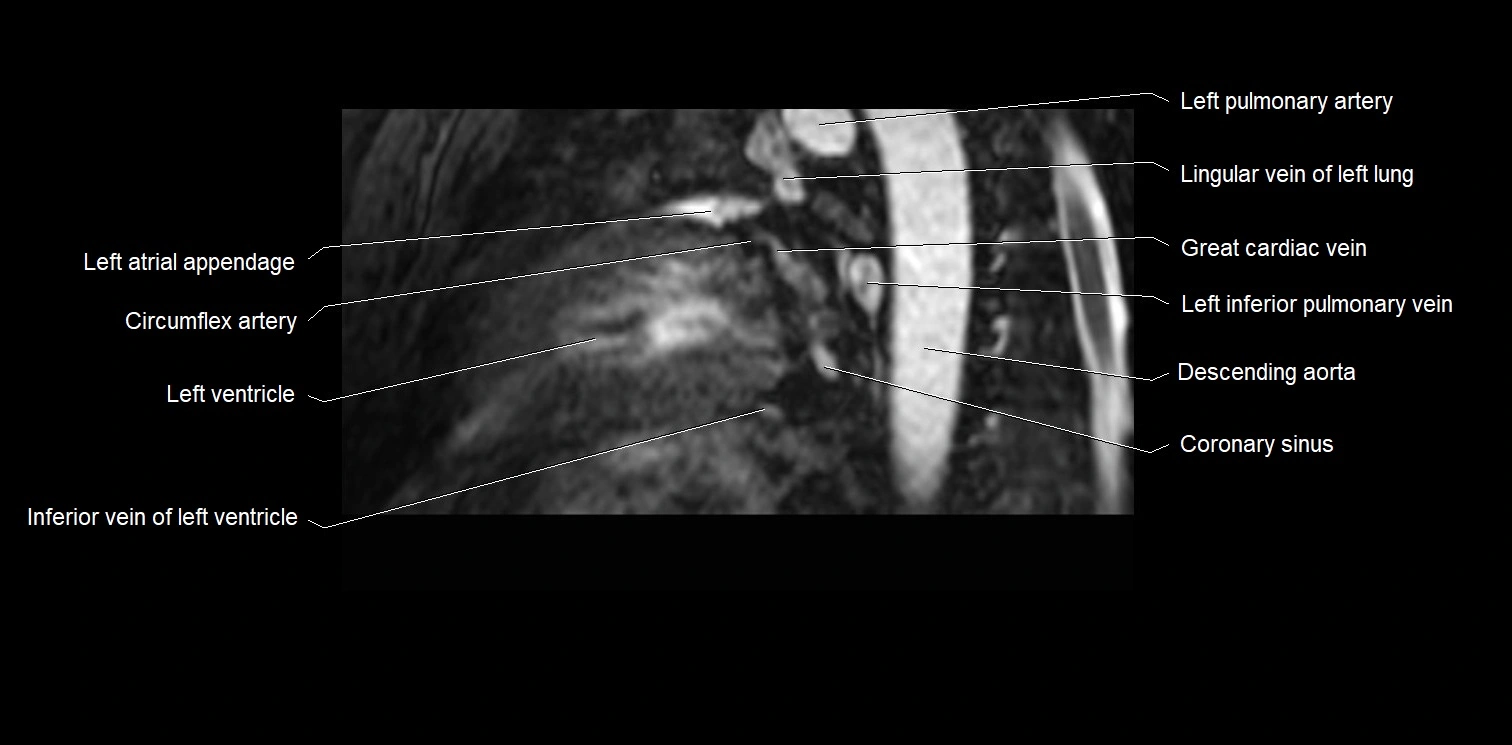

MRI image